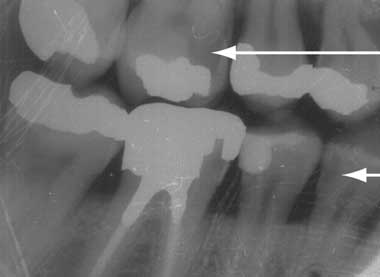

3 Intraoral bitewing x-ray showing crowns of molar and premolar teeth on the right side

Areas of radiolucency (arrows) denote carious lesions. Neither the caries in the upper first molar (beneath an amalgam filling) nor that in the lower first premolar (on the surface adjacent to the next tooth) will be visible clinically.